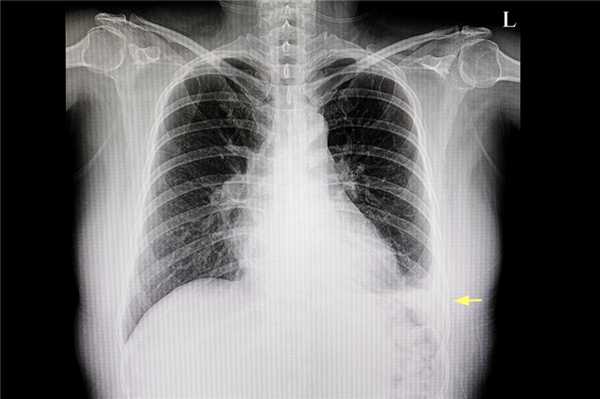

Рентгенологическое изображение легкого пациента, где виден плевральный выпот (желтая стрелка)

Первичный осмотр проводит врач-терапевт , врач общей практики или пульмонолог . Дальнейшее ведение больных осуществляется профильным специалистом: кардиологом , гепатологом, нефрологом, эндокринологом . В стационаре пациента наблюдает торакальный хирург.